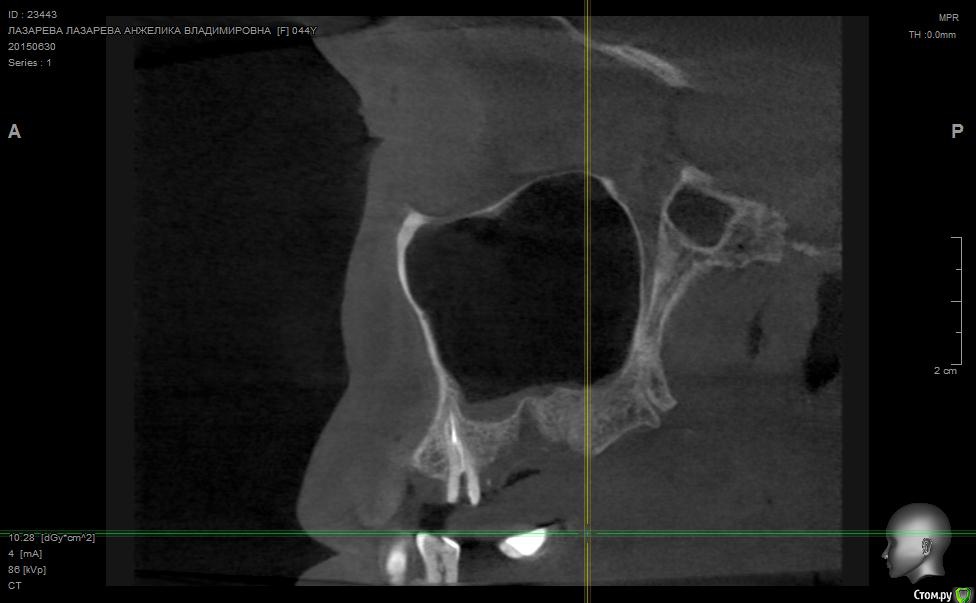

Angelika Опубликовано 2 июля, 2015 Поделиться Опубликовано 2 июля, 2015 Добрый день!Помогите,пожалуйста!!!!!!8 мая имплантолог(!) удалил 2 зуба-27(резерцин-формалиновый) и 28 (нелеченный).Удаление было очень долгим и травматичным,почуяв неладное,хотела убежать прямо из кресла.Последствия-одонтогенный гайморит,не считая незаживающих лунок .В начале июня отлежела в ЧЛХ(антибиотики,физио).26 июня сделала КТ.Нос пришел в норму более-менее,а вот челюсть....((((( Из заключения: 26,27,зубы отсутствуют. В альвеолярном отростке верхней челюсти в области отсутствующего 26 и 27 зуба визуализируется дефект костной ткани размерами до 9,6*14,0*7,2 мм с неровными и нечеткими контурами, с множественными мелкими и крупными секвестрами, с разрушеннымиоральной кортикальной пластинкой альвеолярного отростка верхней челюсти на протяжении до 12,9мм, и вестибулярной замыкательной пластинкой на протяжении до 19,1 мм. Рентгенологическихпризнаков свидетельствующих о наличии свищевого хода, ороантрального соустья - не выявлено,целостность нижней стенки левой верхнечелюстной пазухи полностью восстановлена на всем протяжении. Положительная динамика от 26.05.15г. В альвеолярном отростке, в области корней отсутствующего 28 зуба, определяются нечеткиеконтуры лунки удаленного зуба и единичный фрагмент корня размерами до 1,9*1,7*2,7 мм. В областиотсутствующего 28 зуба и бугра верхней челюсти слева визуализируются единичные мелкие участки остеопороза костной ткани альвеолярного отростка верхней челюсти, в следствие исхода воспалительного процесса. Посоветуйте,пожалуйста,нужно ли удалять обломок корня 28 зуба,если он такой маленький,а лунка уже затянулась.Что мне делать,как это залечить,болит вся челюсть с левой стороны.(((((( О имплантах и забыла уже,восстановиться бы после такой травмы.....Помогите!!! Что делать,как залечить все это?Снимки прилагаю. Ссылка на комментарий

Alejandro Опубликовано 2 июля, 2015 Поделиться Опубликовано 2 июля, 2015 На бумаге страшнее, чем на снимке. Лучший врач для Вас теперь - время. Со временем, кстати, станет понятно: что делать с остатком корня, экстренности пока никакой нет. Успокойтесь, сложные удаления довольно часто встречаются. Очень хорошо, что нет ороантрального сообщения. 2 Ссылка на комментарий

Bier Опубликовано 5 июля, 2015 Поделиться Опубликовано 5 июля, 2015 нет. У Вас на рентгене картина свежего удаления. Т.е. в рамках нормы 2 Ссылка на комментарий

Bier Опубликовано 7 июля, 2015 Поделиться Опубликовано 7 июля, 2015 думаю, что проблем там нет. На снимке все не так плохо, как в описании. Все хорошо будет. Ссылка на комментарий